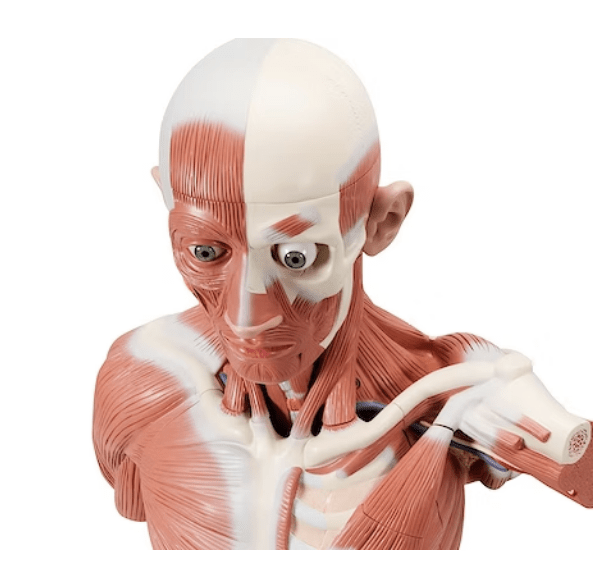

Hoved og hals, 5 dele

Med denne model får du det komplette overblik over hovedet og halsens anatomi. Modellen illustrere både den overfladiske og dybereliggende muskulatur, og viser desuden kar og nerver i relation til disse.

Modellen kan adskilles i 5 dele, idet kranietoppen kan aftages, og hjernen kan udtages og adskilles i 3 dele.

Modellen har målene 36 x 18 x 18 cm (højde x længde x bredde), vejer 2 kg og leveres på en hvid stander, som ligeledes er aftagelig.